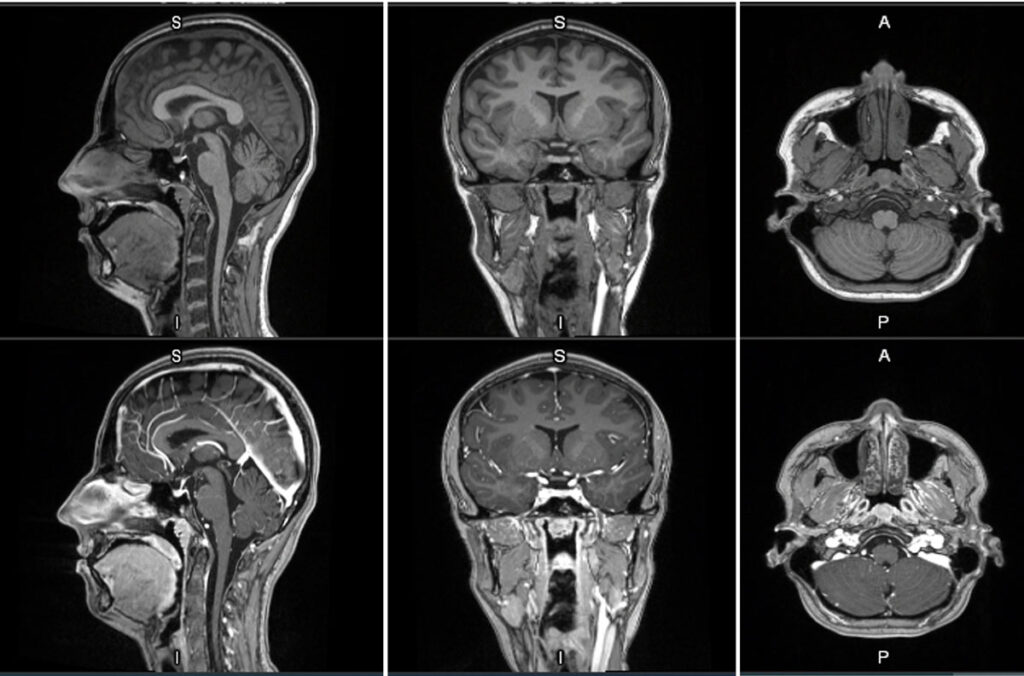

MRI contrast agents enhance the visualization of abnormal structures or lesions during imaging procedures and help clinicians better distinguish between healthy and diseased tissue. Mangaciclanol is intended for general-purpose MR imaging and demonstrates comparable relaxivity (the ability to enhance signal intensity) to market-leading gadolinium-based agent, gadobutrol, with early clinical images suggesting similar diagnostic capability. Unlike gadolinium, which is a rare-earth metal, manganese is present in our food, and is an endogenous element, naturally occurring and autoregulated in the body. The macrocyclic ‘cage-like’ structure of mangaciclanol lessens the possibility of retention.